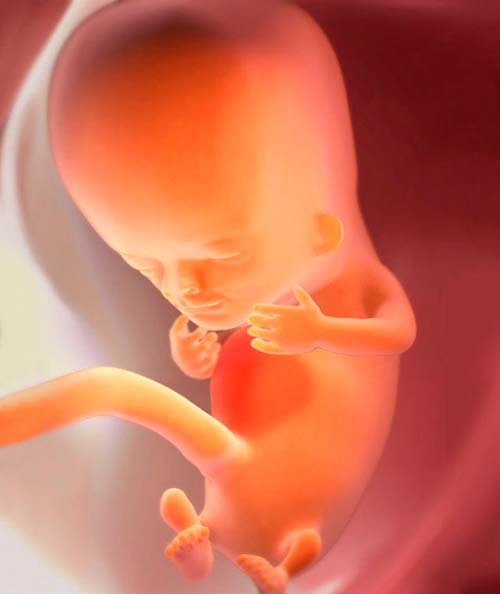

10 savaičių nėštumo laikotarpis vaikui reiškia galutinį visų organų ir sistemų susiformavimą. Šis procesas vadinamas organogeneze ir dabar yra beveik baigtas.

Dabar negimęs vaikas nebelaikomas embrionu. Mediciniškai tai yra vaisius. Ir savo išvaizda - mažas stačiakampis vyras, stambaus braškio dydžio. Mažo kūno ilgis yra maždaug 31–42 mm, o svoris - apie 5 g.

intrauterinė vaiko raida po 10 savaičių

1. Vaisiui dar nėra pilnų kaulų, tik kremzlė. Jo tankis pradeda kilti.

2. Veidas jau suformuotas, tačiau veido, ryklės ir kaklo raumenys dar tik pradeda formuotis.

3. Būsimų plaukų pradmenys atsiranda visame kūne.

4. Smegenėlėje vystosi nerviniai ryšiai, kurie vėliau „įveda“ refleksus.

5. Širdis veikia sustiprintu režimu ir padaro 150–170 dūžių per minutę.

6. Vaikas aktyviai juda: pasilenkia, praplečia galūnes, gali net pradėti čiulpti pirštą. Jei kojos liečia vaisiaus šlapimo pūslės sieneles, kūdikis yra gana pajėgus išstumti. Bet tai nejaučiama - vaikas per mažas.

7. Mažos ausys yra beveik baigtos.

8. Nervų sistema pradeda dalintis į centrinę ir periferinę.

9. Susidaro diafragma - specialus raumuo, skiriantis krūtinę ir pilvo ertmę.

10. Pamažu formuojasi pirminių dantų užuomazgos.

11. Paprastai uodega išnyksta.

Štai vaisius: